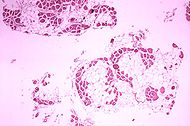

Muscle biopsy

If DNA testing fails to find the mutation, a muscle biopsy test may be performed. A small sample of muscle tissue is extracted and a dye is applied that reveals the presence of dystrophin. Complete absence of the protein indicates the condition.

Over the past several years DNA tests have been developed that detect more of the many mutations that cause the condition, and muscle biopsy is not required as often to confirm the presence of Duchenne's.